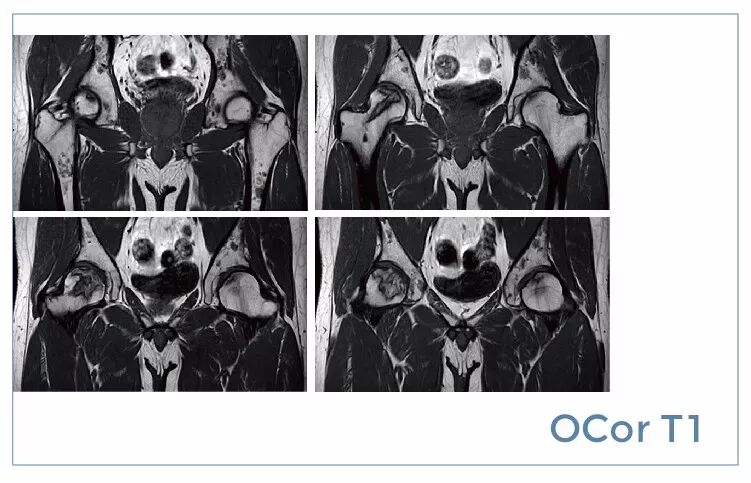

【朗润影像档案】20190719磁共振影像病例结果讨论